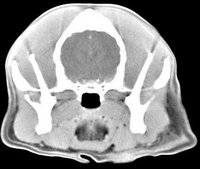

imágenes de TC en el perro | ||||||||||

ejemplo de imágenes de TC en el perro. Nótese la celulitis en la región parotídea izquierda | ||||||||||